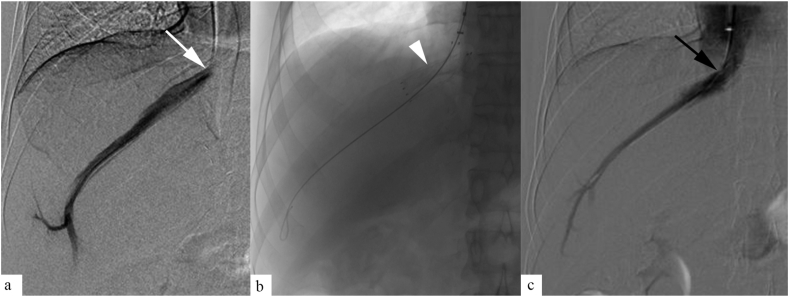

Figure 6.

A 40-year-old male patients presenting with refilling ascites at 18 months following liver transplantation. Venogram (a) showed tight stenosis at suprahepatic segment (white arrow) with trans-stenotic pressure gradient of 11 mmHg. Balloon angioplasty was done using 20 mm balloon catheter (b, black arrowhead). Postprocedure venogram (c) revealed improved flow through the IVC (black arrow), with reduction in trans-stenotic gradient to 3 mmHg.

Figure 7.

A 38-year-old male patient, presenting with refilling ascites, 1 year following liver transplantation. Venogram (a) revealed tight stenosis at the hepatic vein ostium (white arrow). Primary stenting was done across the stenosis (b, white arrowhead). Postprocedure venogram revealed good flow through the stent (c, black arrow).